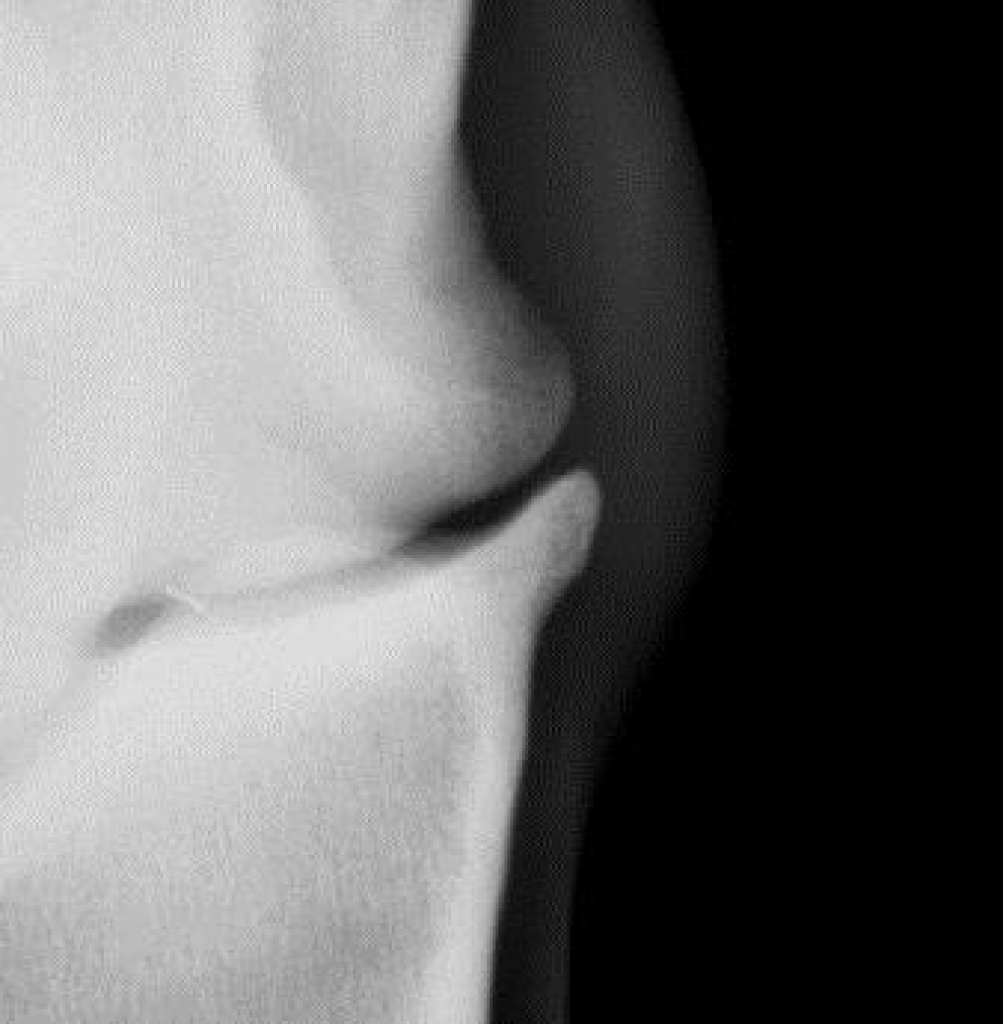

Uitvergroting van hetzelfde gewricht.

Door een kleine beschadiging kan uiteindelijk soort vicieuze cirkel ontstaan waarbij de kwaliteit van het kraakbeen langzaam aan steeds slechter wordt. Als gevolg van de schade aan het kraakbeen gaat ook het onderliggende bot reageren, het gaat aan de randen van het gewricht nieuw bot vormen. Dit is op een röntgenfoto goed zichtbaar als scherpe randjes of bot nieuwvormingen rond het gewricht. Het kraakbeen zelf is helaas niet in beeld te brengen met röntgenfoto’s, daarom is op een röntgenfoto in een heel vroeg stadium van artrose nog niks zichtbaar.

De diagnose van artrose is te stellen op basis van röntgenfoto’s. Op de röntgenfoto’s zien we bij artrose vaak veranderingen aan de randen van de gewrichten. Meestal ontstaan er scherpe randen rond het gewricht.